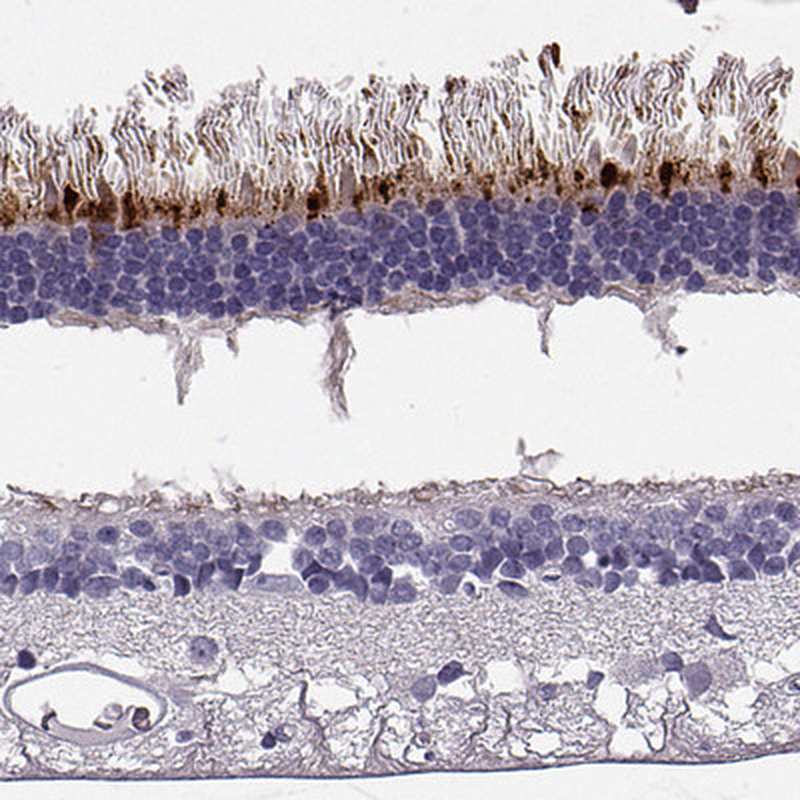

Immunohistochemical staining of human retina shows strong cytoplasmic positivity in rods.